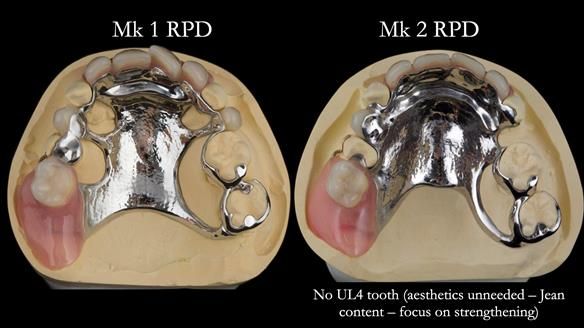

Jean’s Class I Mod III RPD: Learning from My Mistakes – From a Fractured Mk1 to a Stronger Mk2 (4 Years On)

In this edition, I present the removable partial denture treatment for Jean, an 80-year-old woman with a sore mouth caused by a soft tissue-supported 'gum stripper' acrylic denture and a clenching habit. Below, I outline the step-by-step process of her treatment. It wasn't straightforward; I had to remake the denture after it fractured to achieve a satisfactory result. Each patient is unique, and sometimes a new RPD serves as a prototype. Occasionally, I need to make adjustments, learn from any mistakes, and refine the design to get it right.

The treatment has been a success over the past 4 years.